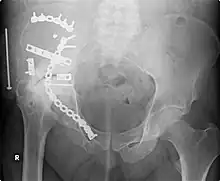

This image, taken in September 2006, shows extensive repair work to the right acetabulum six years after it was carried out (2000). The onset of arthritis, a bone/joint disease, has made further joint damage visible.